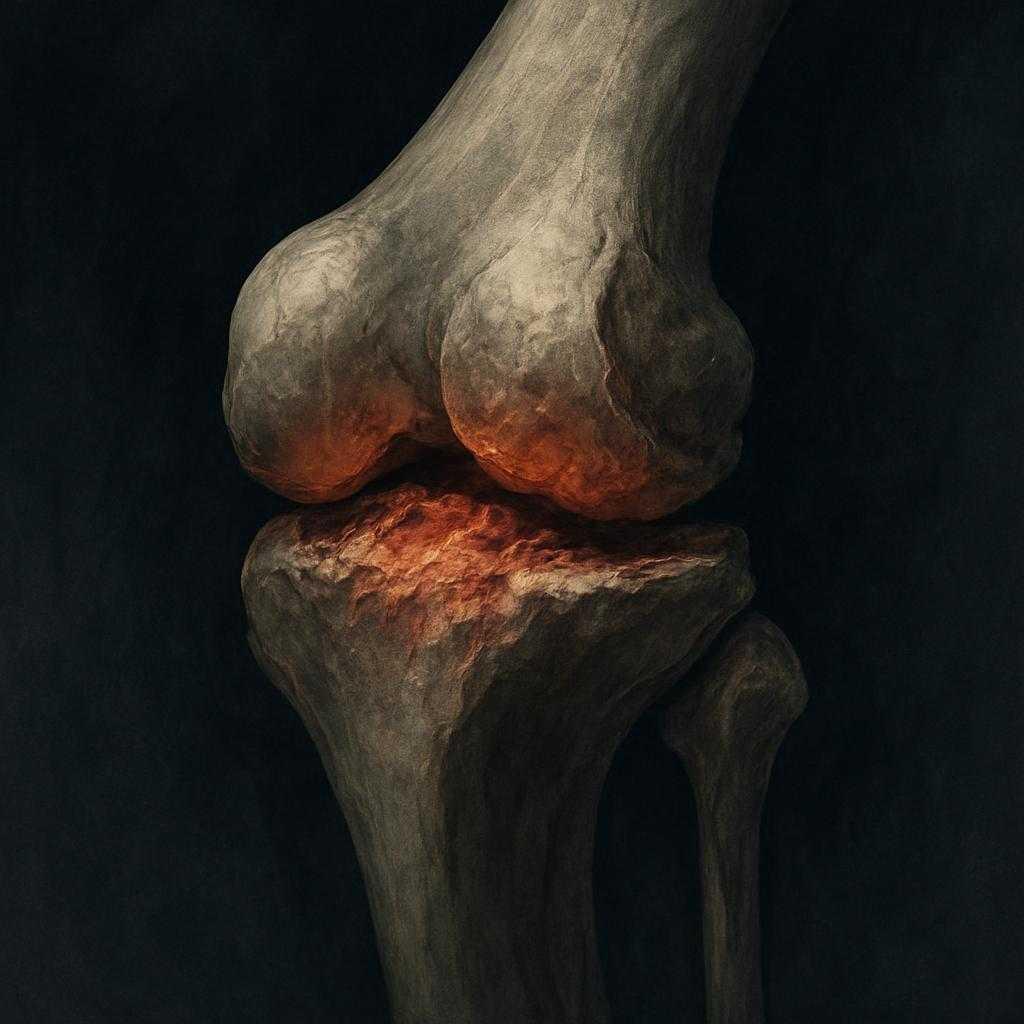

שחיקת סחוס בברך (אוסטאוארתריטיס) היא אחת מהתופעות הנפוצות ביותר במערכת השלד והשרירים, המשפיעה על כ-25% מהאוכלוסייה הבוגרת בישראל. מדובר במחלה ניוונית המתפתחת בהדרגה עם השנים, שבה הסחוס- הרקמה האלסטית העוטפת ומגנה על קצות העצמות במפרק הברך, נשחק ומתדלדל. תהליך זה גורם לכך שהעצמות מתחככות זו בזו, ועם הזמן עלולים להופיע כאבים עזים, נוקשות, נפיחות והגבלה […]

דלקת מפרקים ניוונית (אוסטאוארתריטיס או OA) היא המחלה הניוונית הנפוצה ביותר של המפרקים, המשפיעה על מיליוני אנשים בעולם. זוהי אחת הסיבות המרכזיות לכאבי מפרקים ולירידה באיכות החיים בקרב האוכלוסייה הבוגרת. מדובר במחלה שכיחה במיוחד, המשפיעה על מיליוני אנשים ברחבי העולם, ובישראל בלבד מוערך כי יותר מ- 500,000 איש מתמודדים איתה. השכיחות עולה עם הגיל, אך […]

מי זקוק להחלפת מפרק ברך בסיוע רובוט? ניתוח החלפת ברך מיועד להחליף ברך שנשחקה, הסחוס בברך אט אט נהרס ונעלם מהברך, וגם עצם מפרק הברך שעליה היה בעבר סחוס תקין ובריא, עוברת עם השנים שינויים ניווניים. על מפרק ברך שחוק כמו זה, לא ניתן להצמיח את הסחוס מחדש, ואם תרופות וטיפולים שמרניים אחרים לא משפרים את […]